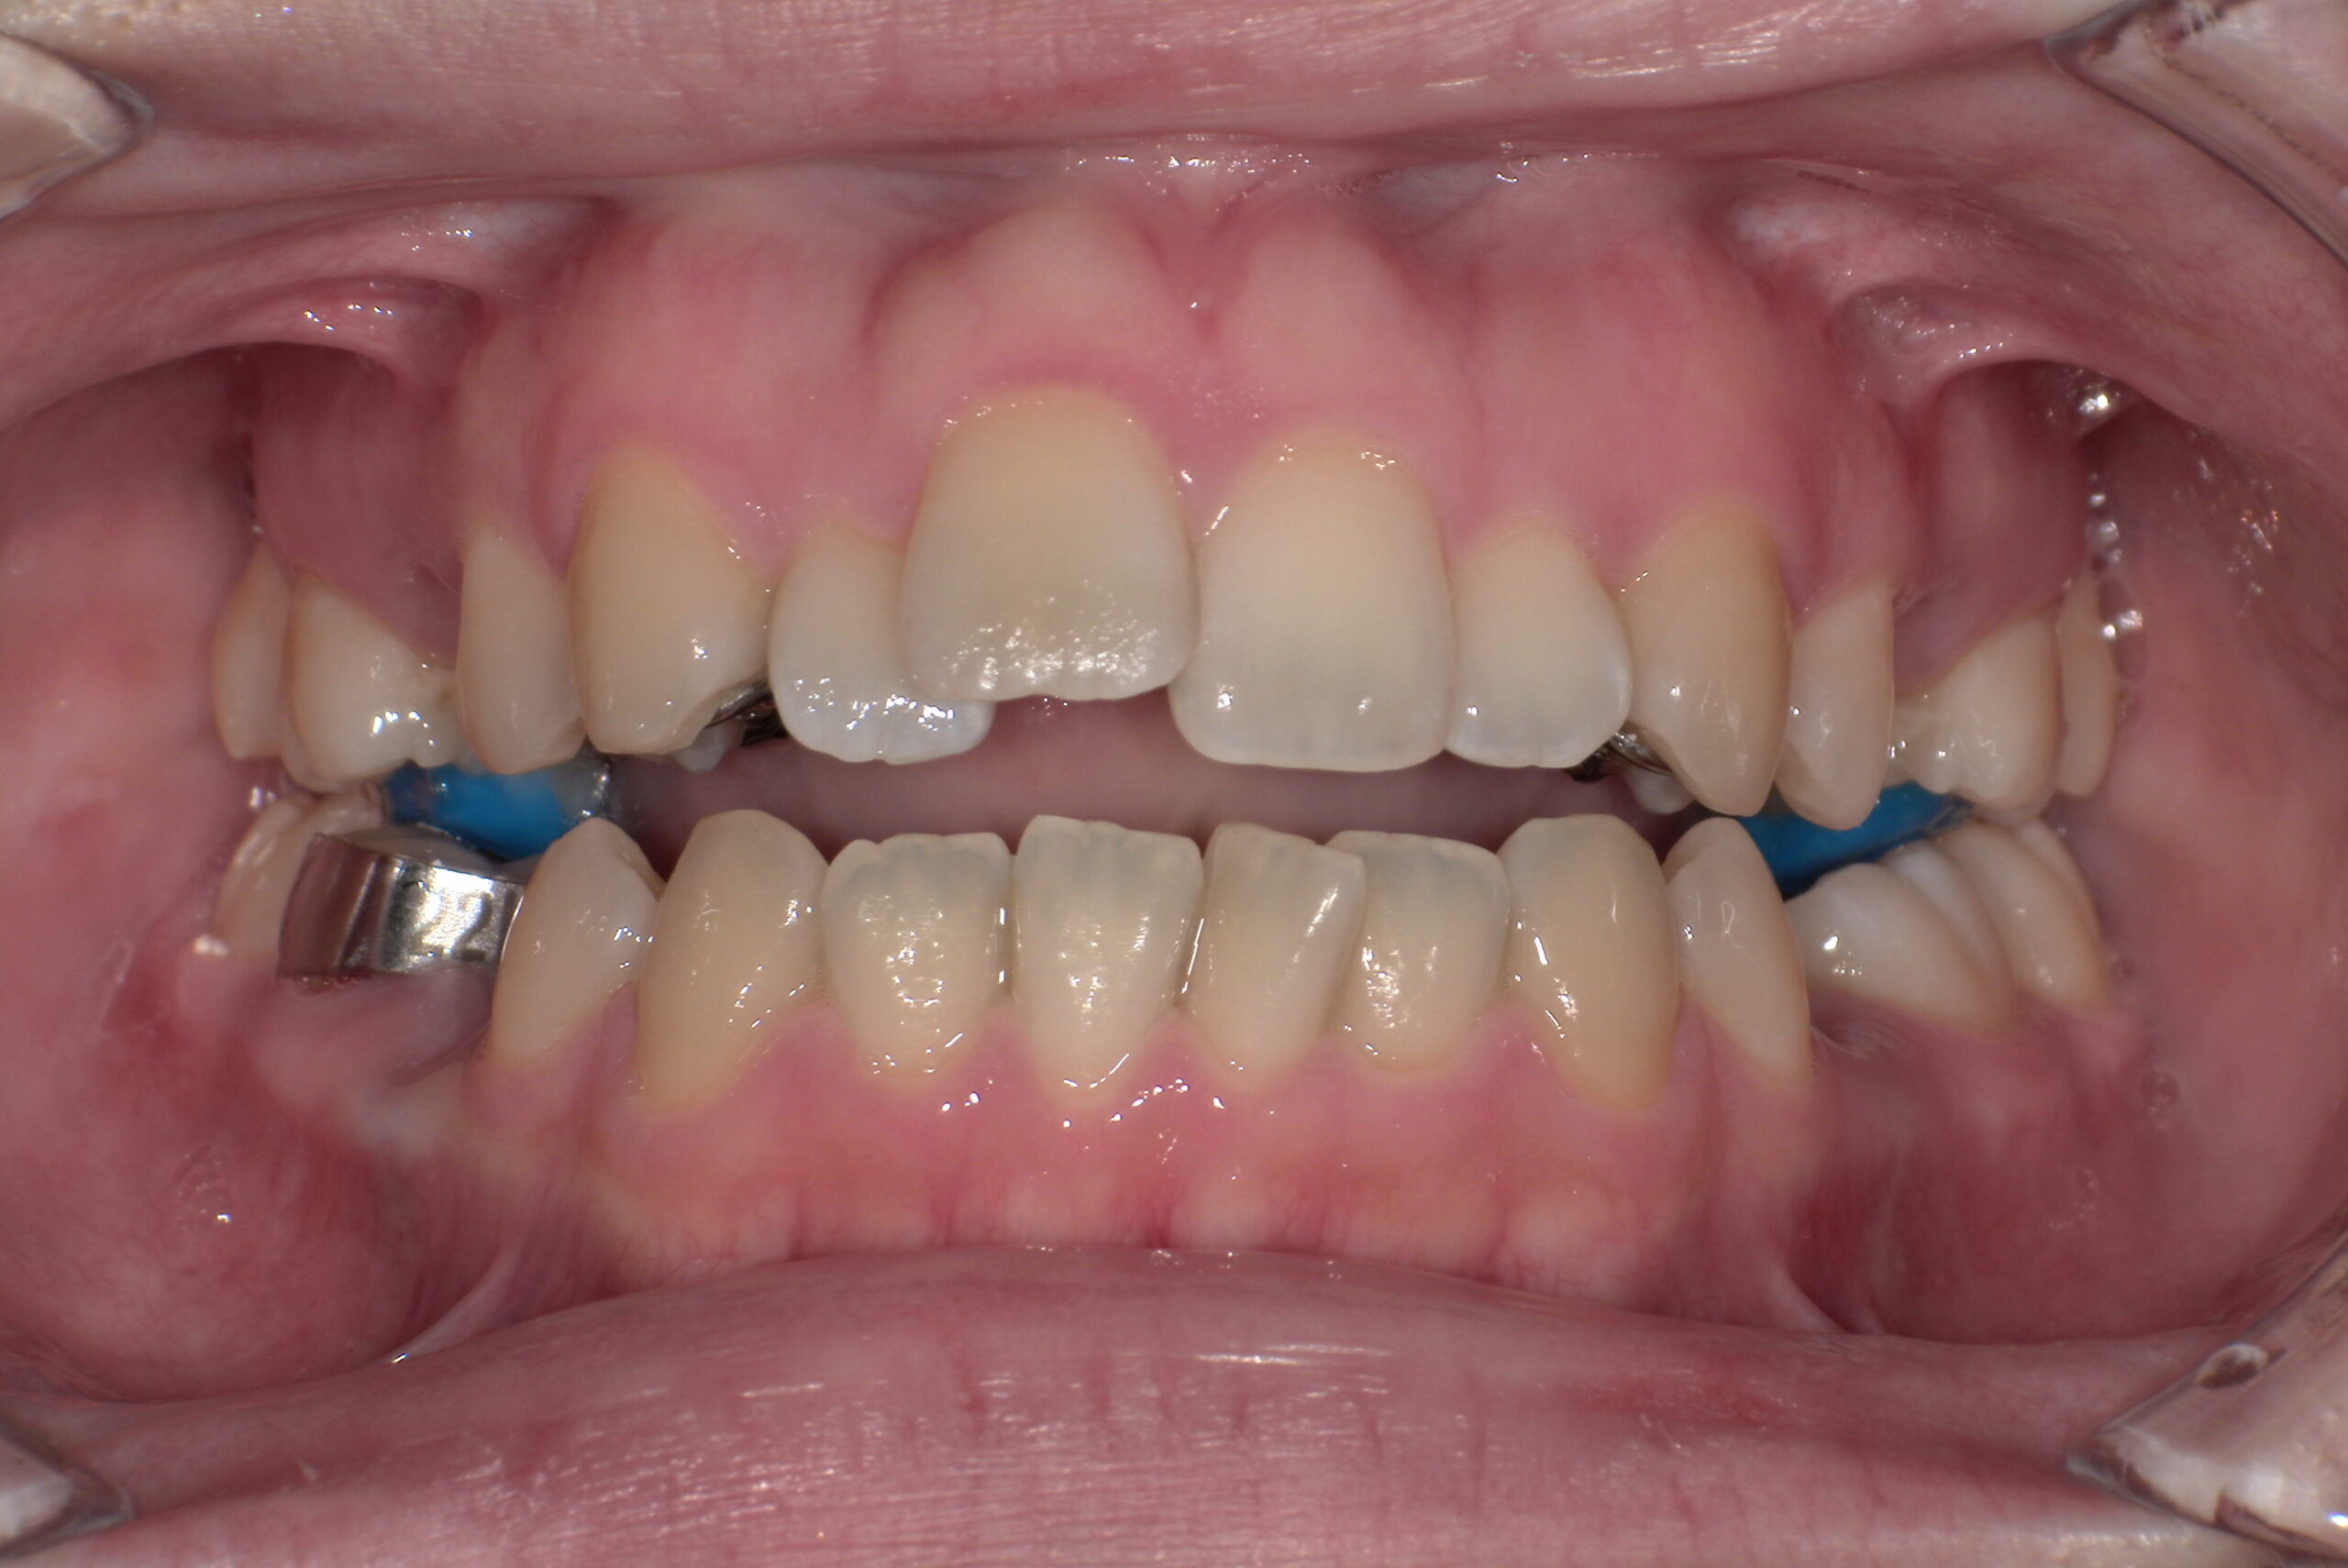

約4か月後

正面

(ゴムかけをして奥歯の咬み合わせや出っ歯の治療をするため、何か所かボタンが付いています)